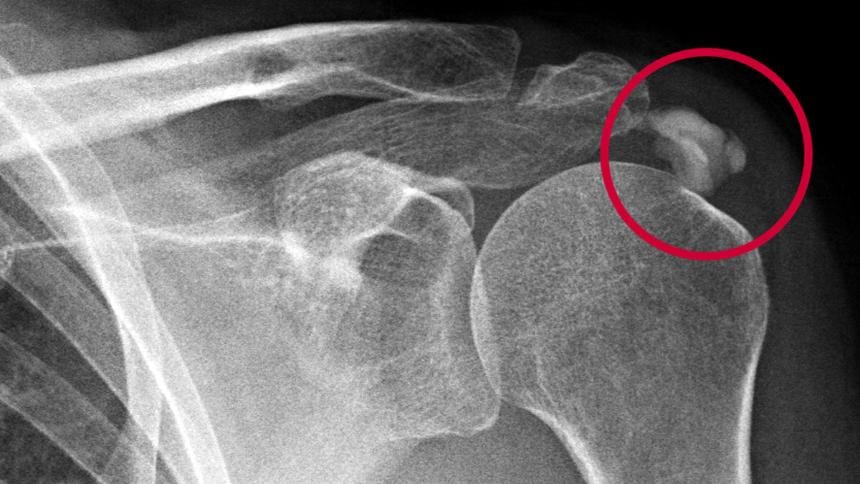

Рентген позволяет выявить очаги кальцификации, сформировавшиеся в коллагеновых волокнах. Визуализация сухожилий во время УЗИ демонстрирует утолщение тканей и снижение их эхогенности. МРТ используется для определения локализации очага воспаления и его размеров.